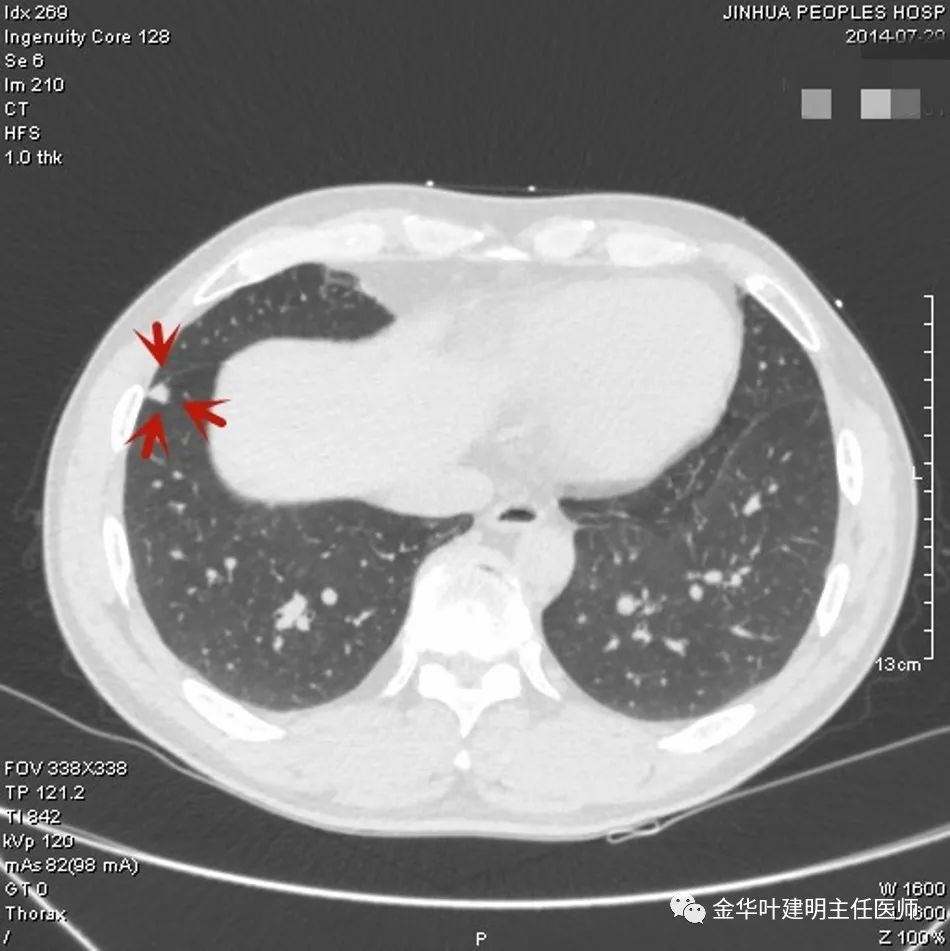

上图示典型的肺内淋巴结影像。靠近胸膜,高密度,三角形工多边形,相对比较孤立,周围没有炎性渗出或卫星灶,邻近胸膜(包括叶间胸膜)但无胸膜牵拉凹陷。